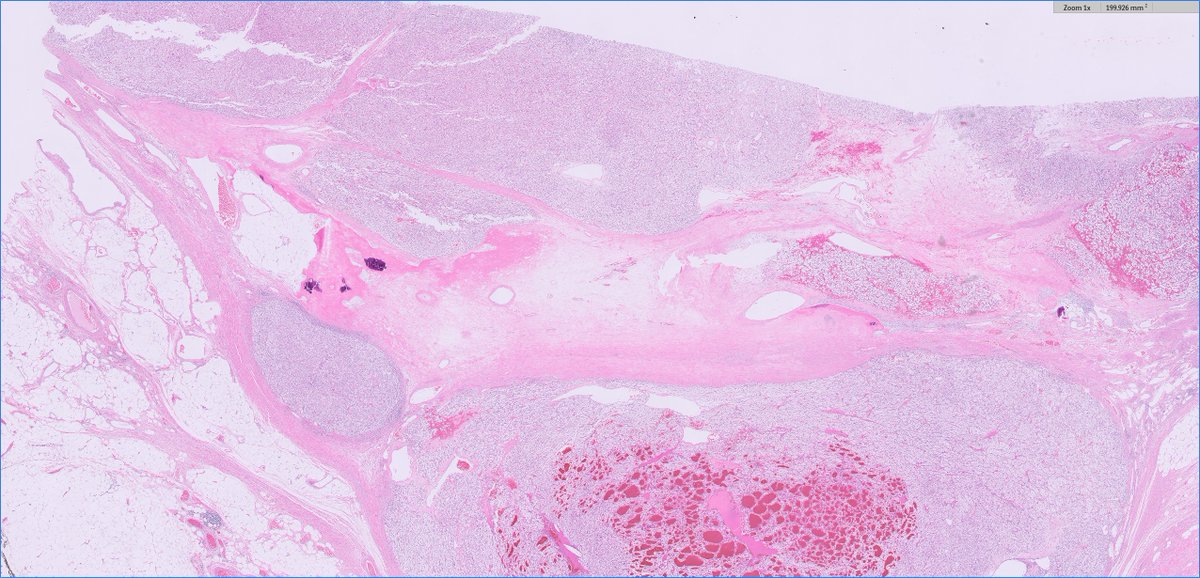

70s F, partial nephrectomy. What is your diagnosis? Gross photo in the chat. #PathTwitter